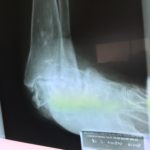

RTG przed